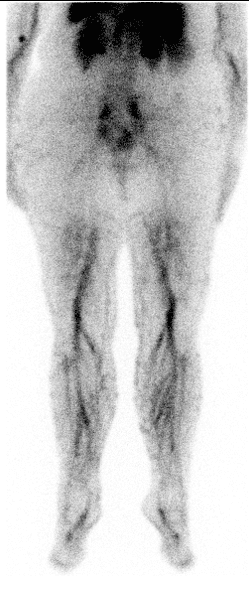

Radionuklidová flebografie je funkční zobrazovací metoda nukleární medicíny využívaná k hodnocení žilního návratu a průchodnosti hlubokého žilního systému dolních končetin a pánve.

Po intravenózní aplikaci radiofarmaka do žilního systému dolních končetin (obvykle dorzálně na noze) je sledována jeho dynamická distribuce proximálním směrem. Záznam umožňuje zhodnotit rychlost, symetrii a kontinuitu průtoku v jednotlivých segmentech.

- Normální nález: symetrický průchod radiofarmaka oběma DK bez známek obstrukce, rychlý transport do pánevních žil a duté žíly.

- Akutní HŽT: absence průtoku v úseku s trombózou, případně zástava postupu radiofarmaka.

- Chronická HŽT: zpomalený průtok, nepravidelná distribuce, přítomnost kolaterál.

- Kolaterální oběh: vizualizace náhradních žilních cest (paravertebrální, povrchové žíly DK).